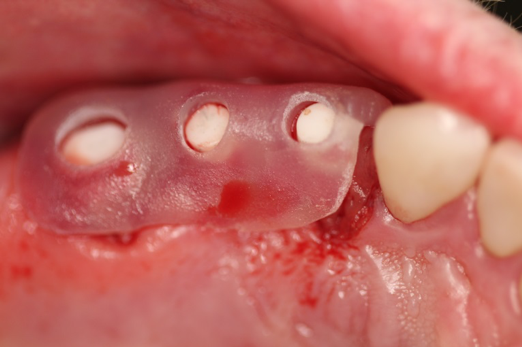

Fig 20. Immediately after extraction and placement.

Figure 20

Occasionally dentists are presented with extreme challenges with long-term restorations and replacing missing teeth. Dentists must evaluate the patient's condition, develop optimum long-term oral health, and attempt to meet the patient's expectations. Figure 18 showed a class III malocclusion with deep bite, multiple abfractions, and less-than-ideal occlusal plane, but the patient wanted to replace his maxillary right canine only. A discussion with the patient regarding occlusal disharmonies and comprehensive recommendations for full-mouth rehabilitation revealed that the patient had a limited budget for dental care. The patient understood the ramifications of his comprehensive dental needs not being affordable. Decisions were made to atraumatically remove the maxillary right canine (Figure 19) and immediately place a ceramic dental implant (Figure 20). Polytetrafluoroethylene (PTFE) 4-0 sutures were placed to help support soft tissues, and then a full-arch Essix-style retainer with a flowable composite facial veneer was used to provide some esthetics during the patient's healing phase (Figure 21). The implant and the retainer were not to be in contactthe retainer may occlude with the opposing dentition and also be passive in relation to the ceramic implant.

Sutures were removed 2 weeks after surgical implant placement, and the patient was instructed to continuously wear his Essix-style retainer for 12 weeks. The retainer was worn while eating during the 12-week period. The patient returned at 12 weeks for soft-tissue and implant-bone evaluation (Figure 22). At this appointment, minimal lingual soft-tissue manipulation was performed by gingival abrasion to the keratinized soft tissue and an aluminum chloride gel was placed.